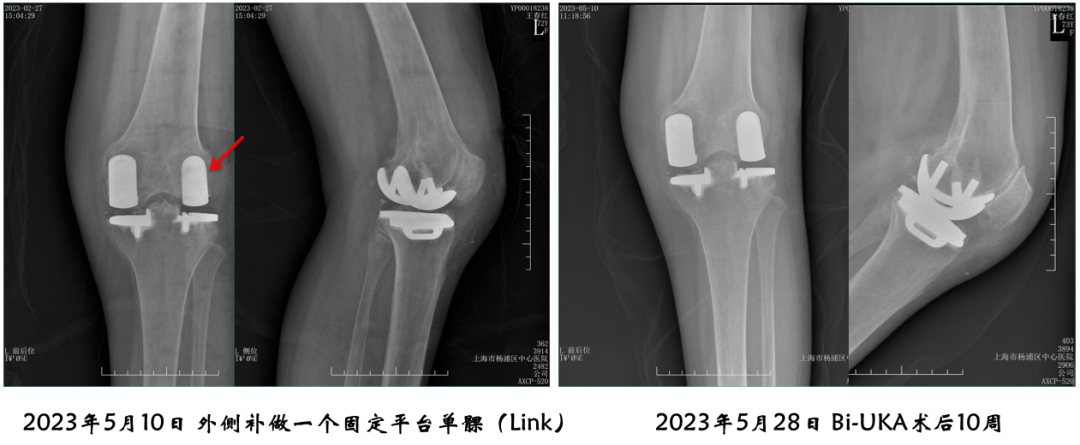

病例4:内侧OxfordUKA术后6.5年外侧进展性OA

病例4:Bi-UKA术后

病例4:Bi-UKA术后Bearing 后脱位的处理